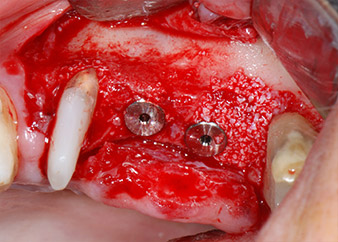

The implants (Restore, Keystone Dental, diameter 3,75 mm, length 8.0 mm) were placed with the implant motor (Figs. 11 and 12).

ready for the cover screws

Fig. 12: Both implants in place and ready for the cover screws.

Bone deficiencies around the implants, at the mesial aspect of tooth 27 and around the buccal root of tooth 24, were filled with xenogeneic bone substitute particles and covered with an absorbable collagen membrane (Bio-Gide, Geistlich Biomaterials) for GBR augmentation (Figs. 13 and 14).